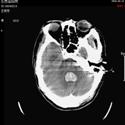

2).脑室出血 行脑室穿刺外引流 术前 术后